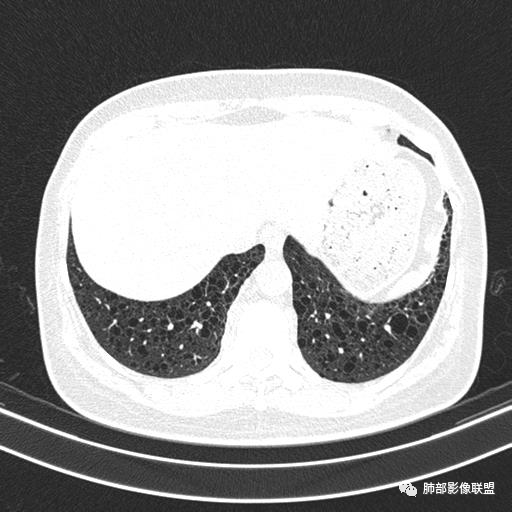

中年女性,不吸烟

双肺弥漫囊腔,累及肋膈角,囊腔形态相对规则单一。

符合LAM

CT平扫示双肺弥漫分布大小不等囊状薄壁透光区,无内、中、外带分布差异,间质稍示增厚。拟LAM

女,46,活动性气喘1年。苯吸入史半年。胸部CT:两肺弥漫囊腔,上至肺尖,下至肋膈角,形态类似小囊腔。考虑:LAM,鉴别LIP,BHD,PLCH等。

CT表现:双肺弥漫大小不等的薄壁囊腔,囊壁<2mm,外形规则,血管影多位于囊腔周围,囊腔之间肺组织正常,随着疾病进展到晚期,囊腔变大、增多,不可胜数,囊腔可融合成较大的囊,与肺气肿相似,形成间质性肺纤维化。部分病例可出现结节影。